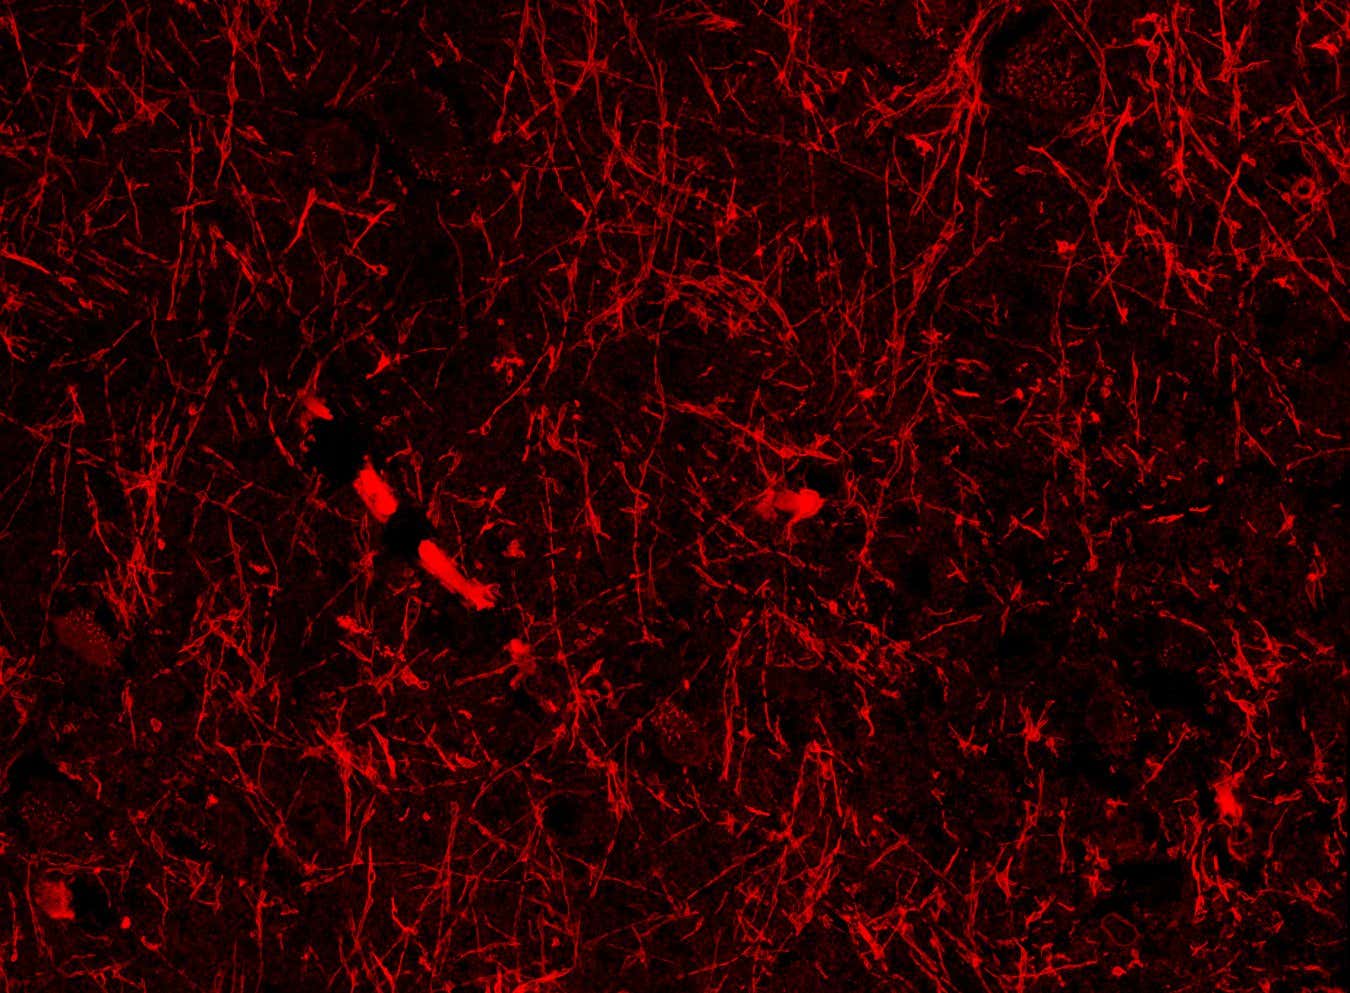

Lymphatic-like structures within the brain of a healthy person

Shiju Gan/Harvard University

Most imaging studies haven’t spotted lymphatic vessels within the brain, only in its protective outer layer. But now, Chongzhao Ran at Harvard University and his colleagues may have discovered a hidden network of lymphatic-like brain vessels inside the brain that connects to the glymphatic system. “This is my most significant discovery in 30 years,” says Ran. “It is the dream of a scientist.”

Team member Shiju Gu, also at Harvard University, accidentally spotted the structures while looking for the protein beta-amyloid in brain slices from mice with an Alzheimer’s-like disease. Beta-amyloid helps neurons function, but it can form toxic clumps – a hallmark of Alzheimer’s – which may accumulate due to poor brain drainage.

When the researchers repeated the experiment in mice with and without an Alzheimer’s-like disease, they consistently found dozens of the vessel-like structures in all the brain regions they sampled, including the cortex, which is involved in thinking and problem-solving; the hippocampus, which helps us form memories; and the hypothalamus, which controls sleep and body temperature.

The structures seemed to wrap around the brain’s blood vessels and meningeal lymphatic vessels – found in the outer protective layer – suggesting they help to drain waste via the glymphatic and lymphatic systems, says Ran.

Crucially, the researchers found the tube-like formations in brain samples from someone who died with Alzheimer’s disease. They have also found them in brain tissue from a person who died without the condition, according to Ran.

The team hypothesised that the structures were either a kind of lymphatic vessel, lined by cells that contain or are coated with beta-amyloid, or a form of the protein that can develop into solid fibres that seem to contribute to Alzheimer’s disease, but are sometimes also found in unaffected brains.

To find out, the researchers applied protein markers that highlight lymphatic vessels to brain slices from mice. These consistently stained the tube-like structures, though less strongly than known lymphatic vessels from the same animals. This prompted them to name the structures nanoscale lymphatic-like vessels, or NLVs, and conclude that they weren’t a form of beta-amyloid.